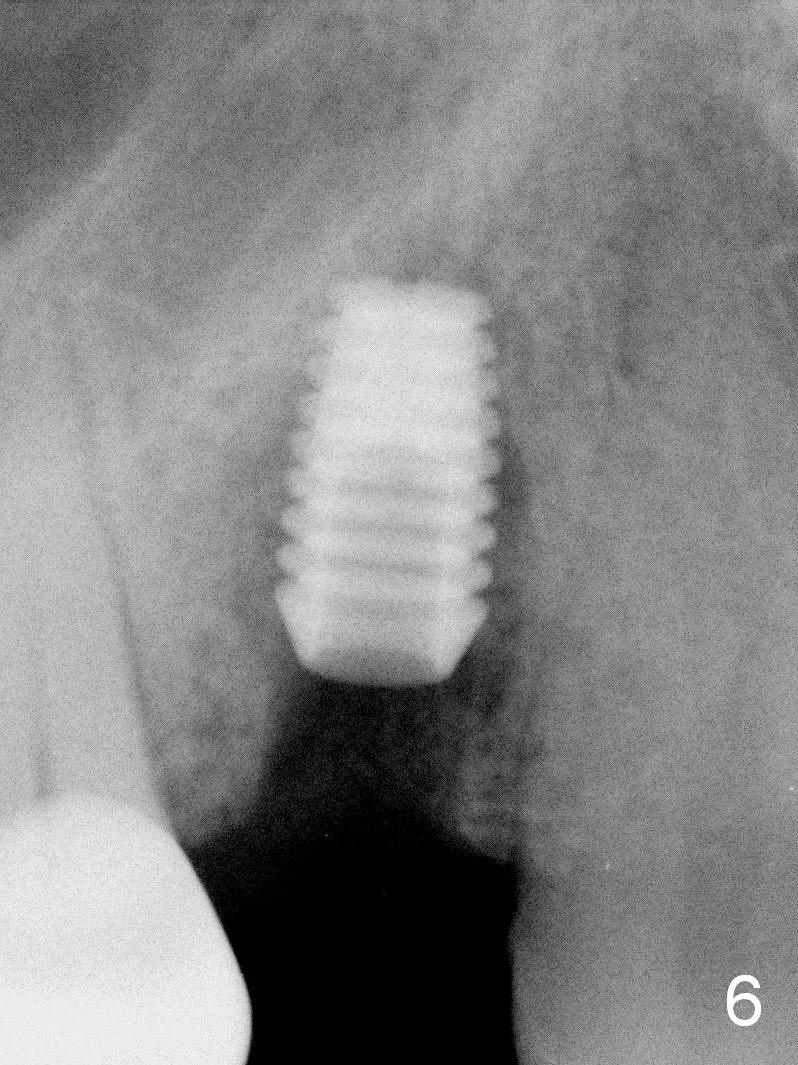

A 68-year-old man has pain and swelling associated with the tooth #5 (Fig.1). The fistula (*) is connected to the periapical radiolucency using a gutta percha (Fig.2 <). There are deep pockets distobuccal and lingual. The lingual root is found to have oblique fracture upon extraction. The distobuccal plate perforates (Fig.3). Collagen plug is placed. The buccal plate is concave (Fig.4) and socket density is low 2.5 months post extraction. Three months post extraction a 4.5x8 mm Bicon implant is placed after reamer and osteotome osteotomy (Fig.6). Bone density around the implant appears to increase 5 months post placement (Fig.7). Porcelain-fused-to-metal crown is cemented 2 weeks later. Bucco-occlusal porcelain chips 2 months post cementation. The patient decides to redo the crown. PA is taken before crown removal (Fig.8: 3 year 10 months post cementation). When a straight abutment is removed (Fig.9 A), a 15° angled abutment has to be used (Fig.10 red) for restoration.